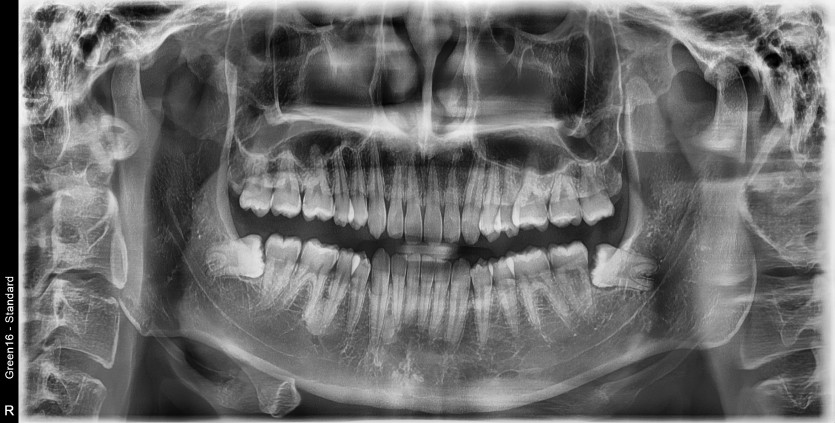

#18,48 사랑니 발치

구강 외과 전문의가 당일 발치했습니다.